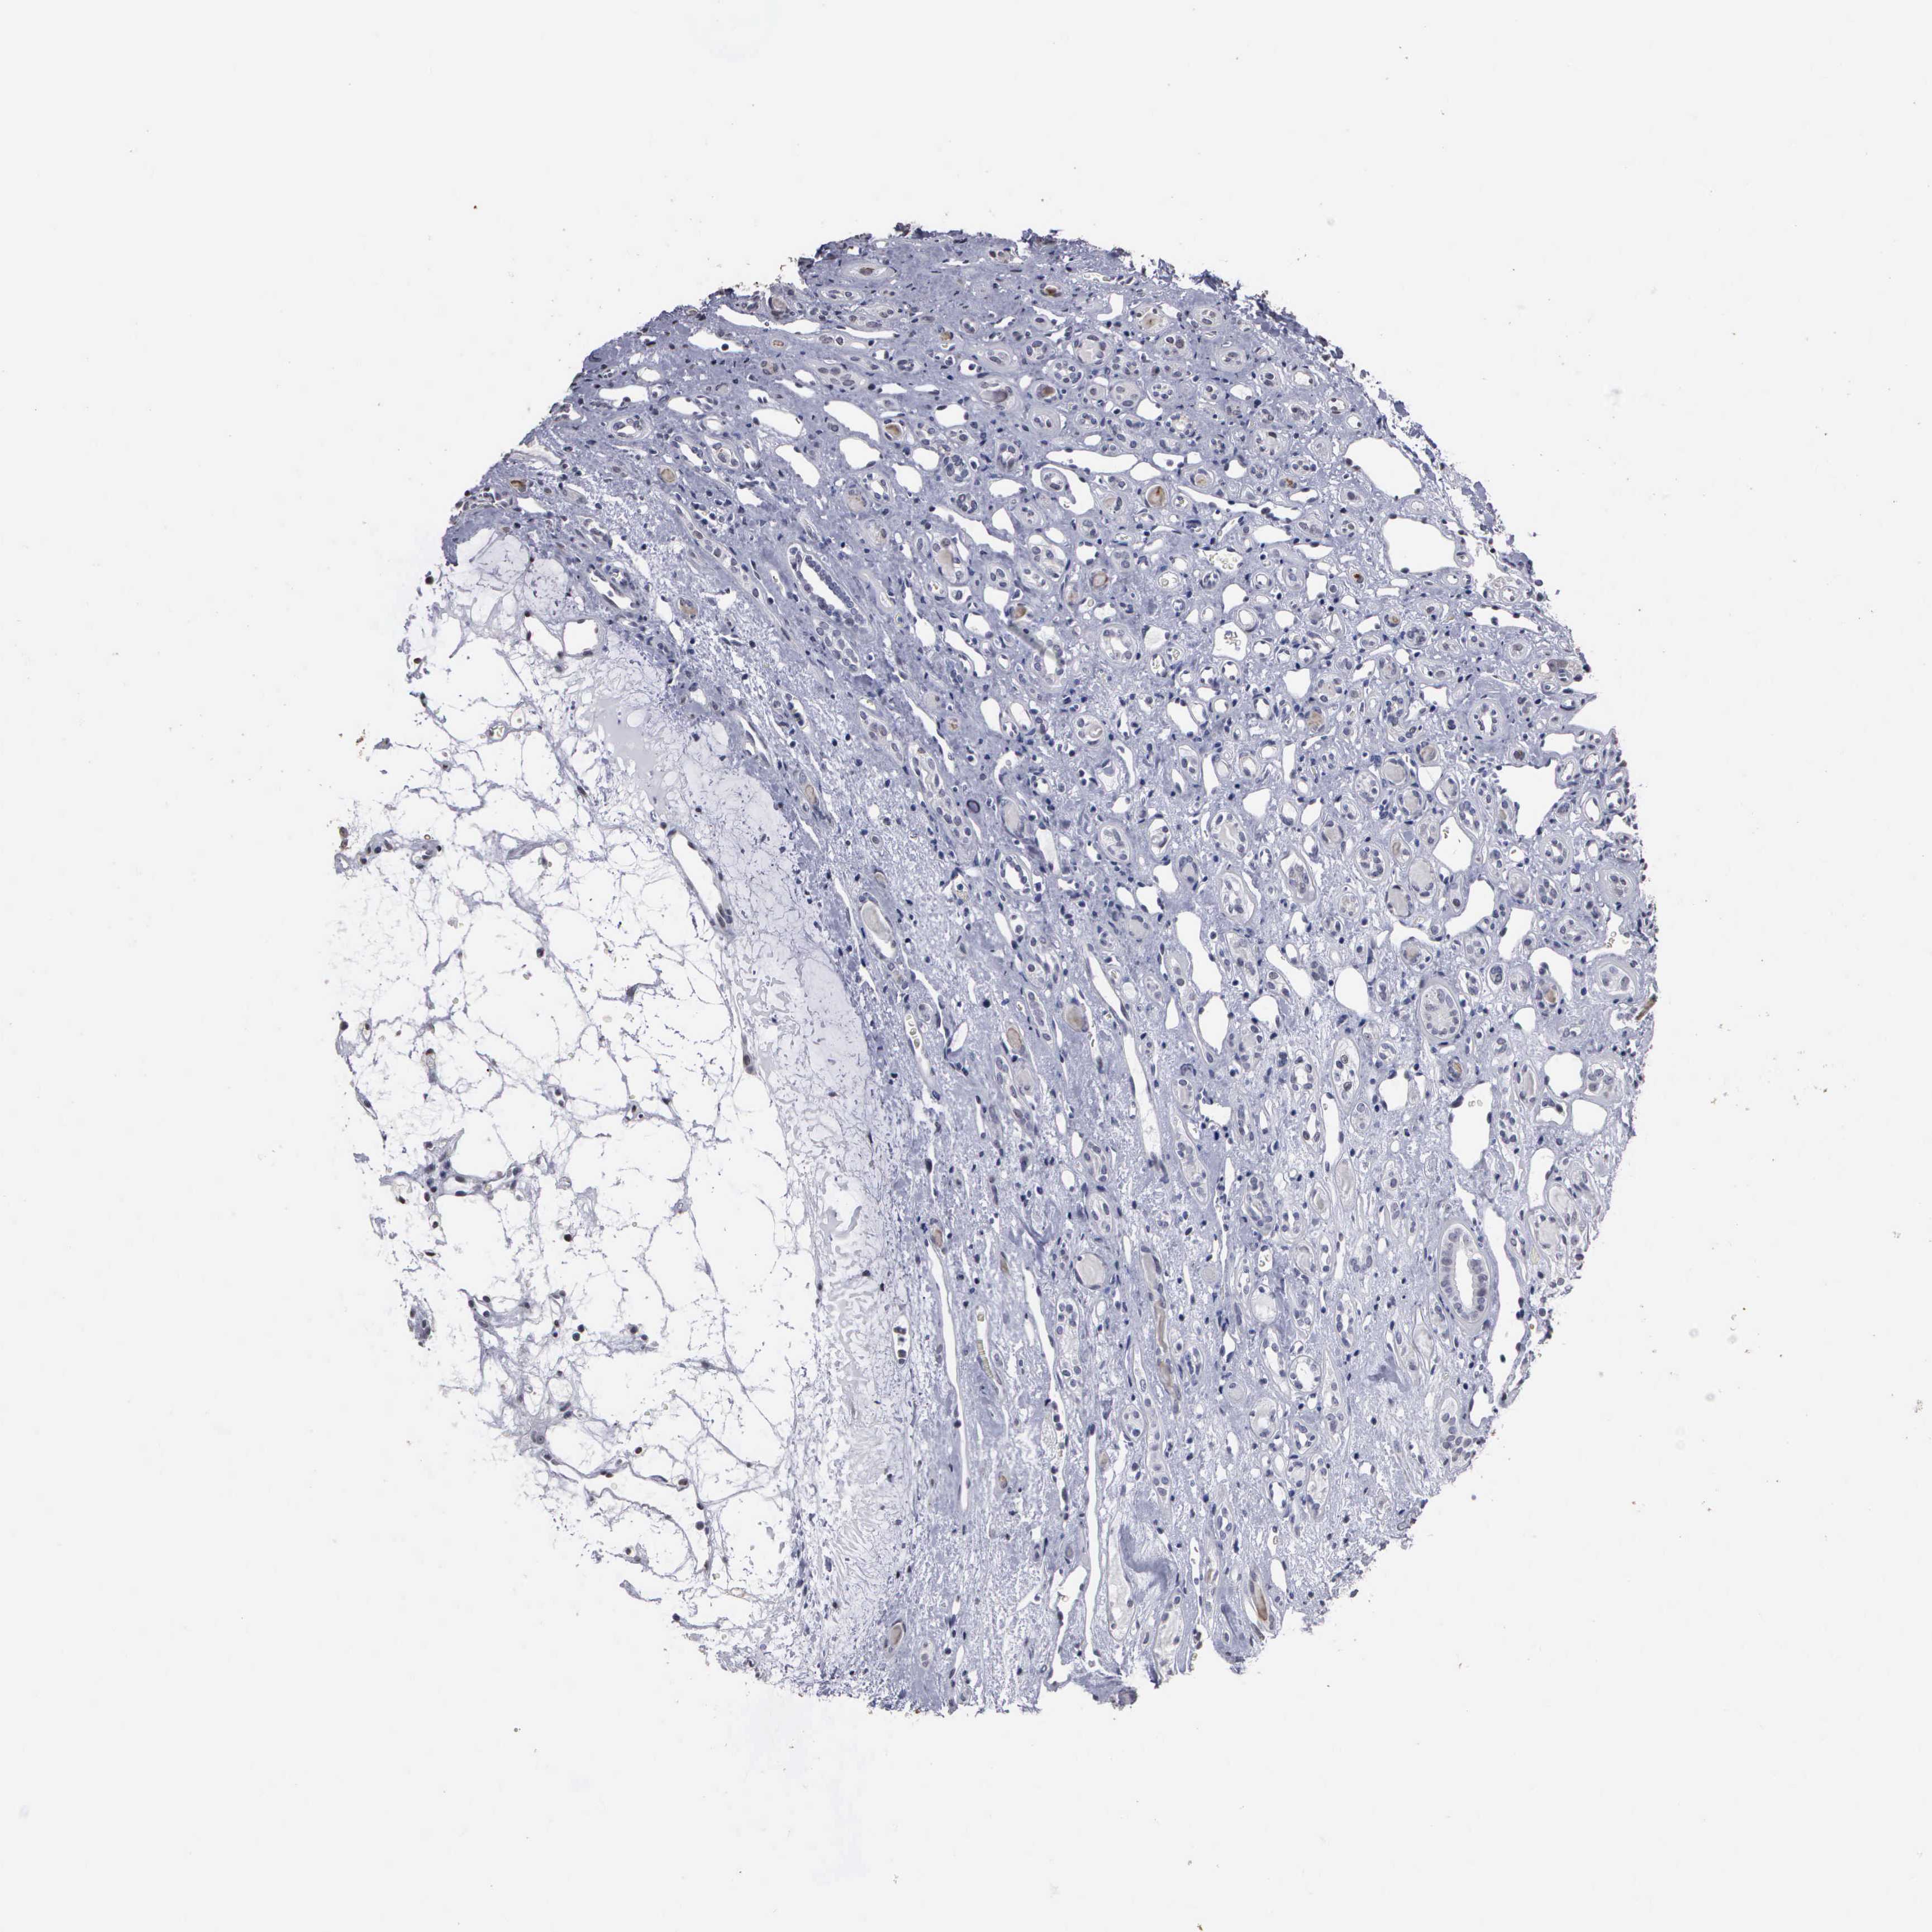

CANCER RENAL CANCER Show tissue menu

KICH TCGA KIRC TCGA KIRC VALIDATION KIRP TCGA PROTEIN RCC CPTAC PROTEIN EXPRESSION